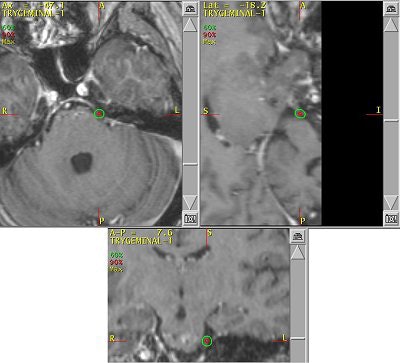

![]() |

| Above, frameless radiosurgery for TN. Below, three months after treatment. Images courtesy of Dr. Kevin Murphy and the University of California, San Diego, department of radiation oncology. |